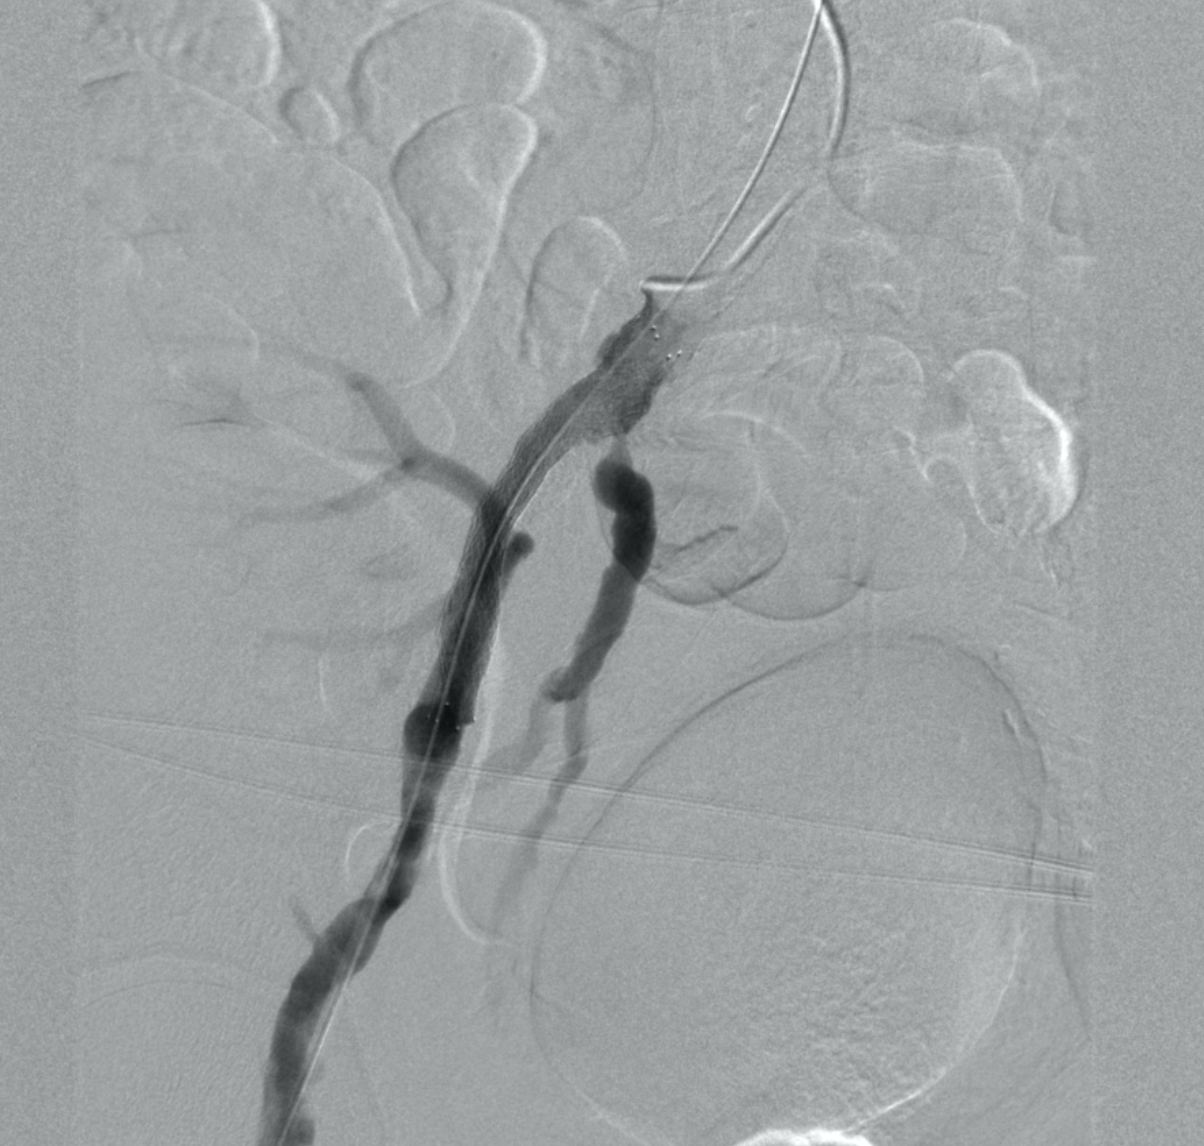

Следующим этапом в область поражения НПА был заведен и имплантирован периферический стент. Выполнена постдилатация в стенте баллонным катетером 10,0х60 мм. На контрольной ангиограмме НПА, БА полностью проходима, отмечается хорошее антеградное заполнение трансплантата почки (рис. 4).

Рисунок 4. Контрольная ангиография после имплантации стента.

При контрольном УЗИ сосудов трансплантата (в сравнении с дооперационным исследованием) наблюдается положительная динамика: увеличились скоростные показатели внутрипочечного кровотока, индексы резистентности (RI) были в пределах нормы.

На фоне проводимой терапии клиническое состояние больного с положительной динамикой, функция трансплантата восстановилась, при этом креатинин снизился до 111 мкмоль/л.